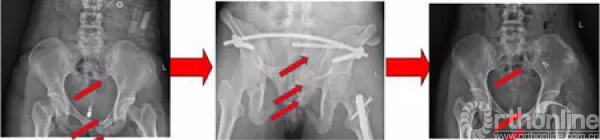

术后复查影像(2017.09.28、2017.10.05)

术后x线(2017.09.17)

骨盆正位、骨盆入口位、骨盆出口位